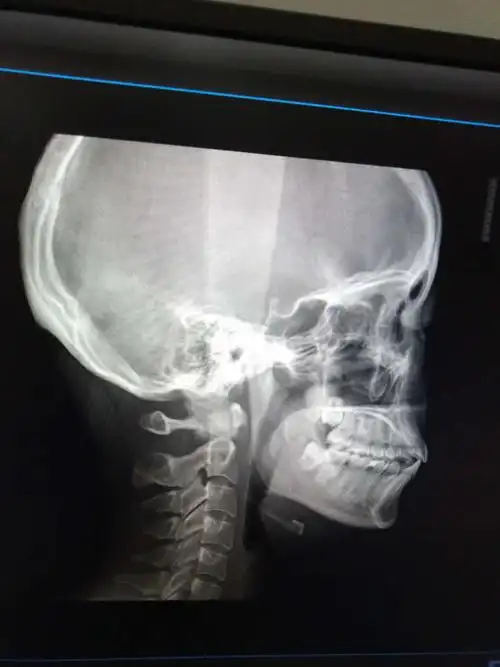

下颌角突出怎么破? - 知乎

你好,我想问下我这个是骨性还是牙性,要是正畸可以改善嘴凸吗希望获得